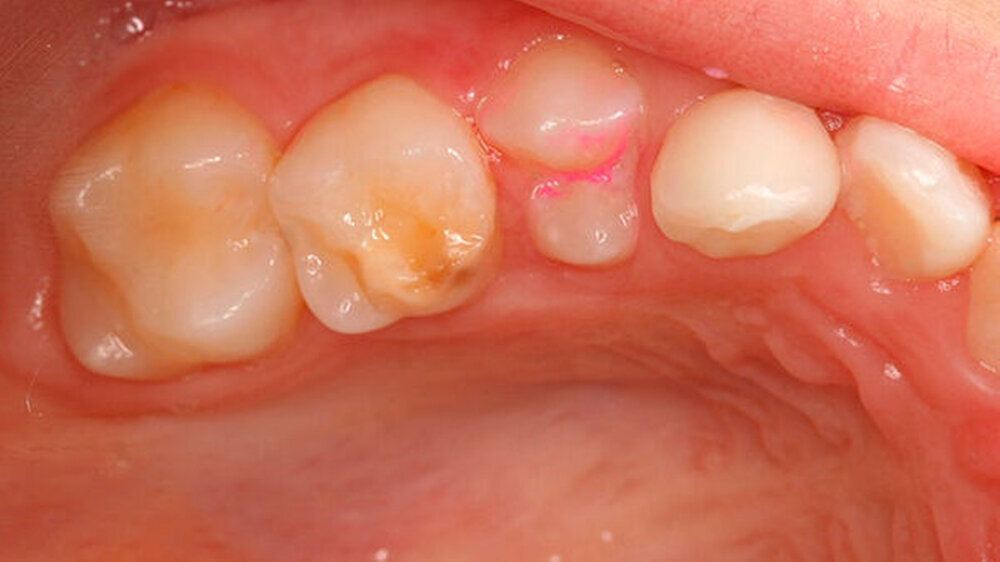

Bei einigen Patienten bestand allerdings auch schon im Milchgebiss eine Neigung zu Hypomineralisationen (Abbildung 3), klassifiziert wurden diese inzwischen als MDH (=deciduous molar hypomineralization) [Elfrink et al., 2012]. Inwiefern eine Hypomineralisation im Milchgebiss aber tatsächlich einen Indikator für eine MIH im bleibenden Gebiss darstellt, ist bisher nicht genauer zu beschreiben [Elfrink et al., 2012].